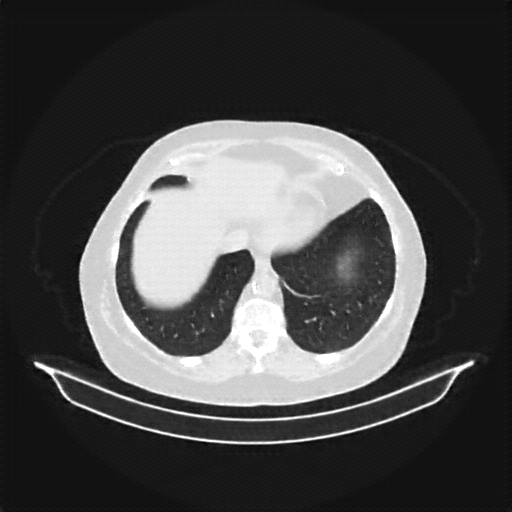

Original VENOUS CT scan

Full window (WL 1023.5, WW 4095 β†’ Low βˆ’1024, High +3071)

Mediastinum window (WL 40, WW 400 β†’ Low βˆ’160, High +240)